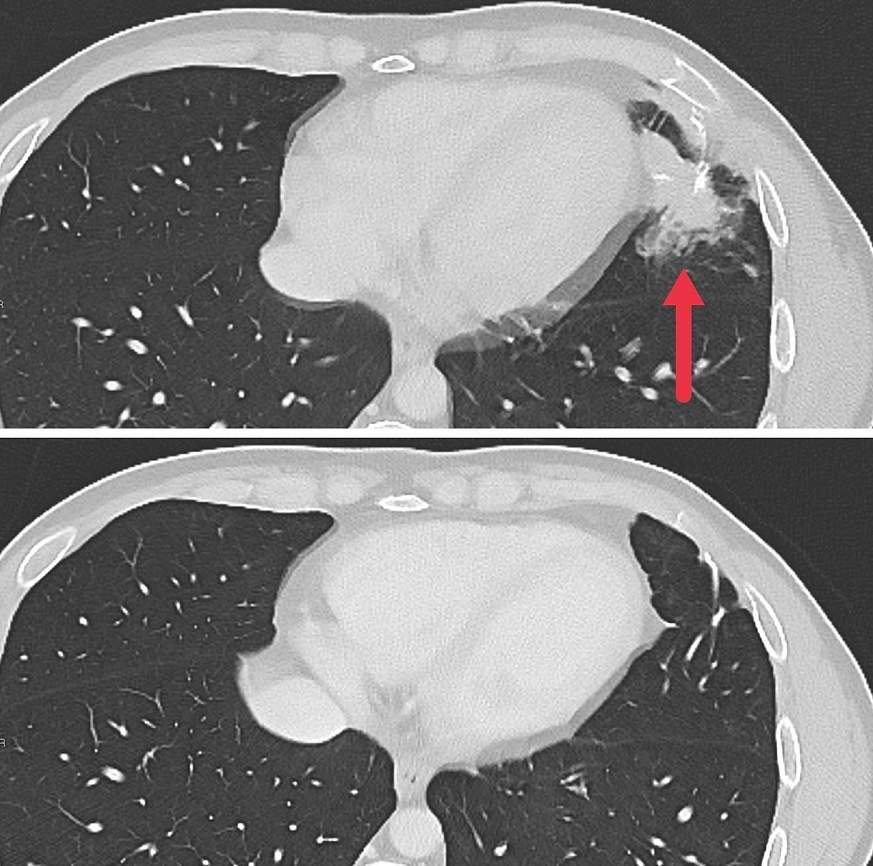

As part of a larger phase 2 trial, seven patients with metastatic colon cancer were treated with the experimental personalized cellular immunotherapy. All seven received several doses of the immunotherapy drug pembrolizumab (Keytruda) before the cell therapy and another immunotherapy drug called IL-2 afterward. Three patients had substantial shrinkage of metastatic tumors in the liver, lung, and lymph nodes that lasted for four to seven months. The median time to disease progression was 4.6 months.